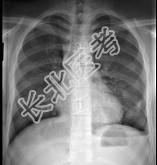

- 单项选择题18岁,男, 被人殴打后胸痛,请结合胸片选出最可能的诊断 ( )

A、血气胸

B、气胸

C、胸腔积液

D、肺气肿

E、肺挫伤